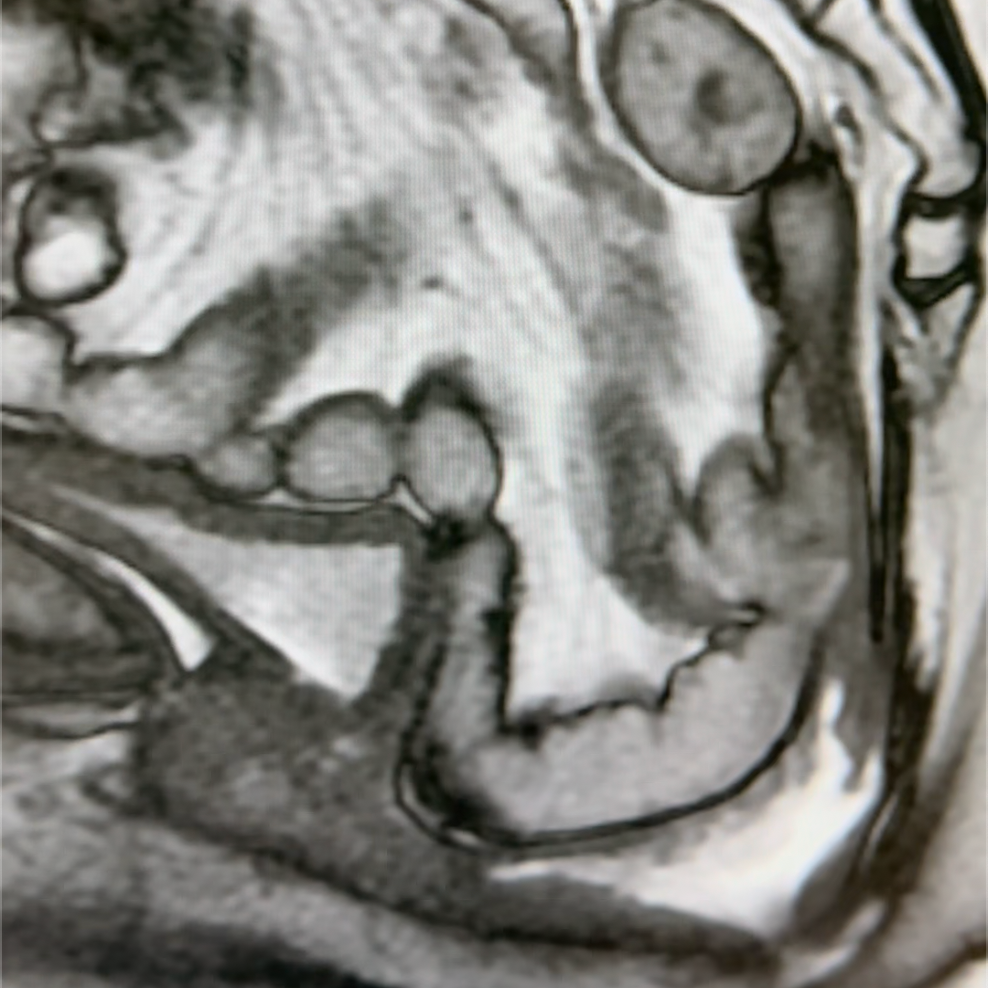

MRI Defecography

Learn how to use MRI to better understand normal and abnormal Pelvic Floor pathology.